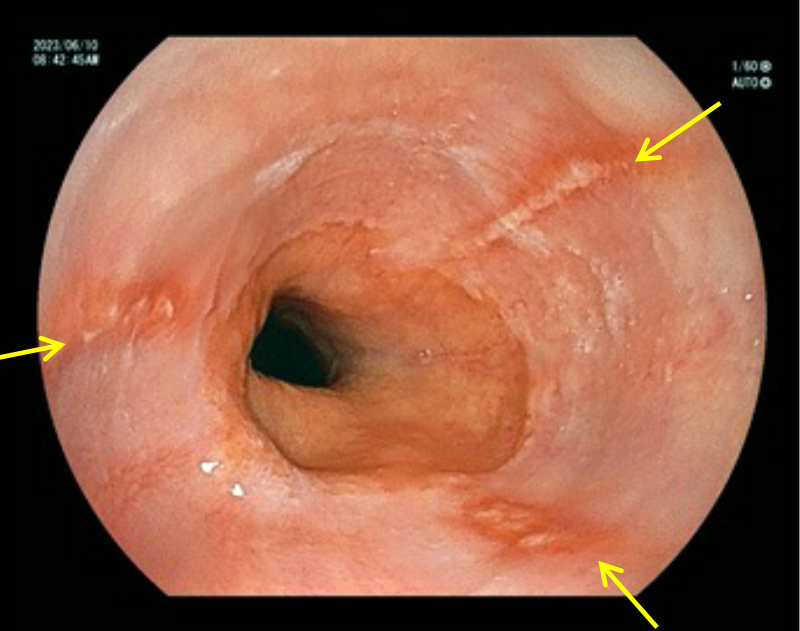

内視鏡検査の所見例

胃体部 アニサキス虫体

内視鏡検査の所見例

胃体部 アニサキス虫体

アニサキス虫体を取り去った後の腫れた粘膜